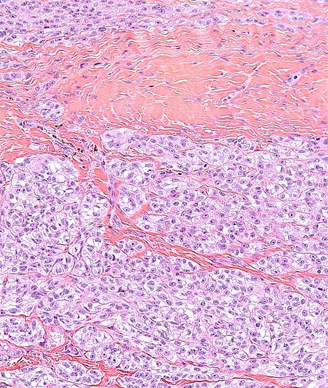

Surgery is the mainstay of treatment for localized soft-tissue sarcoma (STS). It consists primarily of resection of the tumor along with a cuff of surrounding healthy tissue. In limb and trunk wall sarcomas, this basically implies resection of the surrounding soft tissues, which are mainly muscles, subcutaneous fat, and skin.[1] In the retroperitoneum, this necessarily should imply resection of adjacent viscera, even when they are not overtly involved.[2] This is the only way to avoid/minimize the presence of tumor cells at the cut surface (ie, positive microscopic surgical margins). Positive microscopic surgical margins are associated with a higher risk of local failure, distant metastases, and death.[3-6] Moreover, for STS located at critical sites, such as retroperitoneal sarcoma (RPS), positive surgical margins may have a direct impact on survival, favoring the development of inoperable local recurrences.[7] Indeed, unlike with STS arising in the extremities and trunk wall, local control in RPS poses a significant challenge and remains the leading cause of death, particularly in patients with low- to intermediate-grade tumors-roughly 75% of all cases.[8-13] Extending the resection to adjacent uninvolved viscera for primary RPS is the only way to minimize the presence of microscopic surgical margins and hence maximize the chance of cure. In essence, this strategy should often include ipsilateral nephrectomy and colectomy; locoregional peritonectomy and myomectomy (partial/total) of the muscle of the lateral/posterior abdominal wall (usually the psoas) (see Figure); splenectomy and left pancreatectomy, for tumors located on the left upper side; occasionally pancreaticoduodenectomy or hepatectomy, for tumors located on the right side; and vascular and bone resection only if vessels/bone are overtly infiltrated.[2]